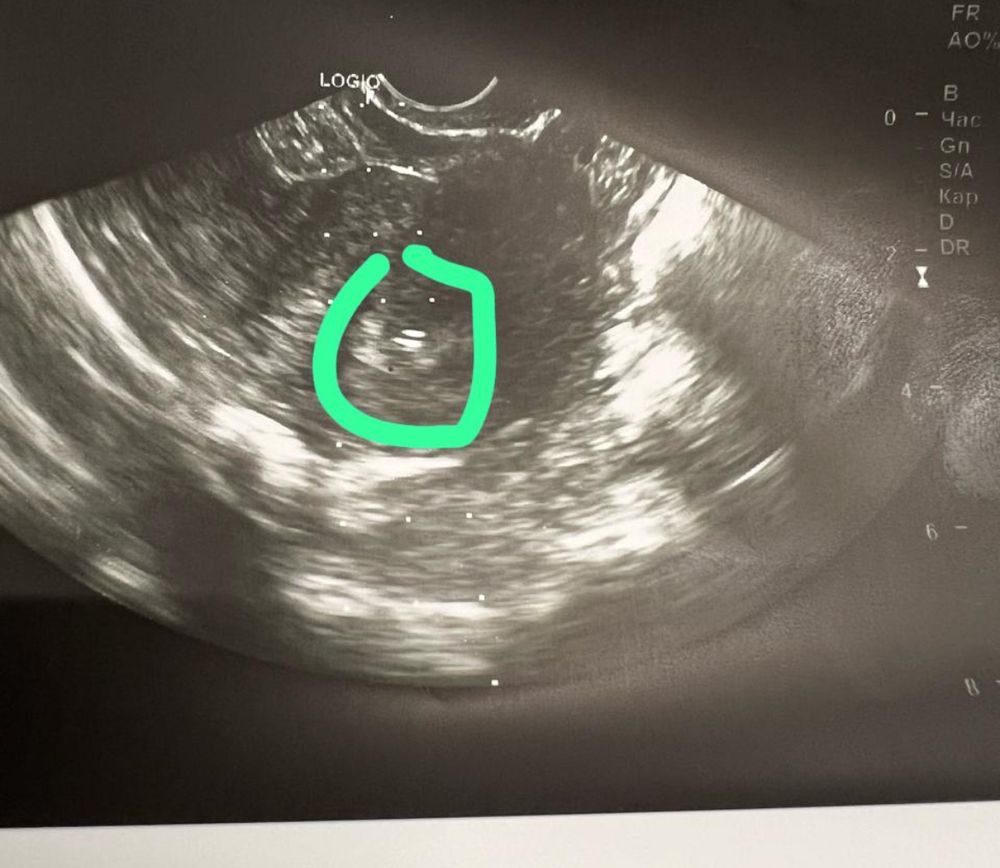

Вот дали снимок после переноса) визуализирую ребеночка и разговариваю с ним. Прошу хорошенько закрепиться)